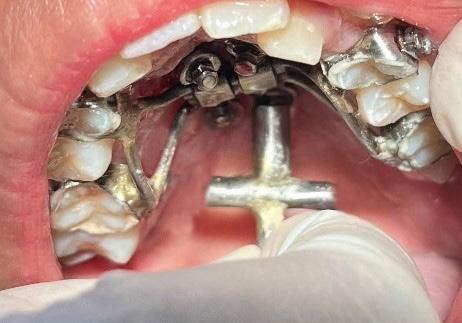

The maxillary cuspids were erupting mesially to the lateral incisors, with very little space to accommodate both teeth without an odontectomy. The expansion was continued (1/4 turn 2x per week), and an attempt was made to create more space for erupting cuspids with an open coil spring (OCS) – between the central incisors and the cuspids (Molar distalization spring, a .010 x .045 - Ortho Organizers). The OCS was measured and cut 4.0 mm longer than the available space. The maxillary arch wire was a .018 SS. An elastomeric chain (EC) was attached from the Hyrax to the lingual button on the lateral incisors. It was necessary to first pull the lateral incisors away from the alveolar process to prevent the break down of the buccal cortical bone around the cuspids (Figure

B, C).

4-A, Figure 3A: The patient transferred to our office, frontal view Figure 3B: The patient transferred to our office, maxilla, occlusal view Figure 3C: The patient transferred to our office, mandible, occlusal view Figure 4A: OCS, frontal view Figure 4B: Hyrax, occlusal view Figure 4C: Retraction of maxillary lateral incisors

To prevent a disto-lingual moment (rotation) of the maxillary cuspids we attached PC from the lingual button on the cuspids to the framework on the hyrax. The anterior portion of the Hyrax was cut off and the remaining portion served as a TP arch for posterior anchorage. At this point, we were 25 months into treatment (Figure 9-A, B, C, D). The hyrax was removed after 30 months of treatment.

placed between the maxillary central incisors and the cuspids, on a .018 ss arch wire.8 The purpose of this center bend is to move the roots apart. A side effect of this center bend is that the crowns have a tendency to move together. Therefore, an OCS was placed between the maxillary central incisors and the cuspids. (Figure 10 – A, B)

After the maxillary cuspids were in contact with the second bicuspids, we had to ascertain that there was adequate width in the inter-radicular space. A center bend - “V” pointing gingivally was

Figure 8A: TADs in situ, frontal view 8B: TAD in situ, right lateral view 8C: TAD in situ, left lateral view 8D: Power arms Figure 9A: Maxilla, occlusal view 9B: Maxilla, occlusal view 9C: Maxilla, occlusal view Figure 9D: After the removal of the Hyrax, occlusal view Figure 10A: Center bend “V” pointing gingivally Figure 10B: OCS between the cuspids and the central incisors Figure 10C: Composite build-ups on the mandibular first molars Figure 10D: Adrian “U” bend spring